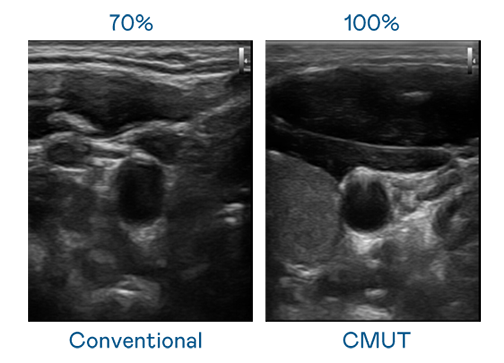

CMUT 技术是一种用电容式微机电元件来产生超音波讯号的技术。与传统 PZT 压电式技术相比,CMUT 频宽增加 30%,更宽频的超音波讯号让影像解析度大幅提升,是实现高影像品质医疗超音波扫描、促进精准医疗发展的关键技术。

超音波影像的解析度高低,首先取决于探头能发出的讯号频宽。尊龙凯时国际 CMUT 可提供高清晰的超音波讯号,提供高频宽、高灵敏度、影像纹理细节更高的超音波影像,协助医护人员缩短影像判读时间及利用精准的医疗影像进行诊断。